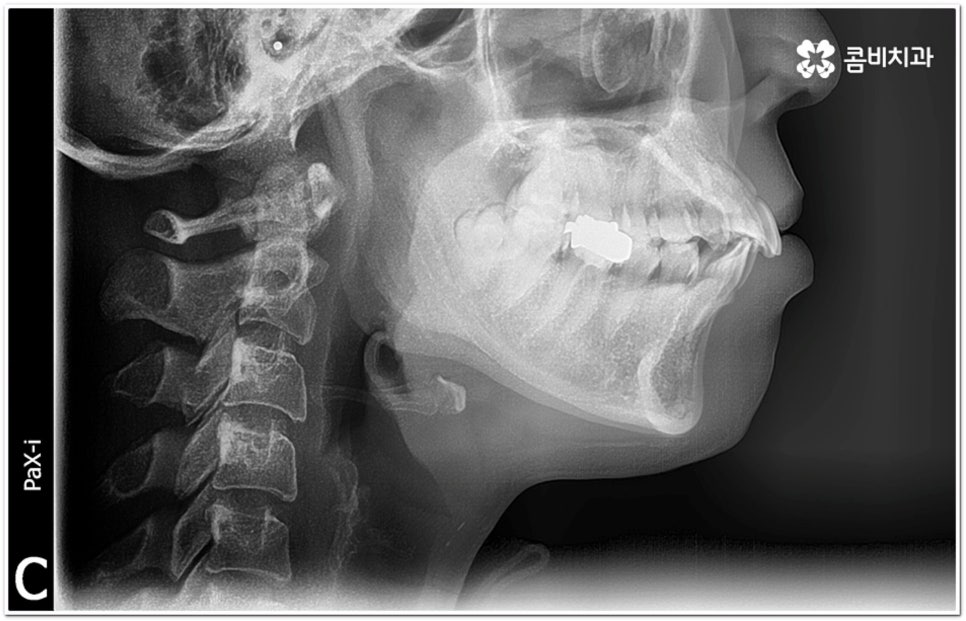

환자마다 치열, 교합, 치아가 튀어나온 각도, 잇몸이 드러나는 정도, 상악과 하악의 구조 및 관계 등 턱관절 관련 부분 상황이 모두 다르기 때문에 3D CT 같은 정밀 검진 기계를 통해 이를 꼼꼼하게 살펴보고 각각에 맞는 계획을 세밀하게 세워 교정 치료를 진행해 줄 필요가 있어요. 이때 환자분들의 상황에 따라 양악수술과 같은 외과적인 방법을 병행해야 하는 케이스도 있을 수 있기 때문에 돌출입을 가지고 계신 분들 중에서 수술에 부담을 느끼고 지레 치료를 포기하신 분들도 있을 수 있는데 정도가 많이 심각하지 않고 구조적인 원인이 크지 않다면 대부분의 케이스는 치아교정 만으로도 충분히 개선이 가능하니 먼저 돌출입교정치과 에 들러서 정밀 검사를 진행한 후 치료 방향에 대해 의료진과 논의해 보시면 좋을 거예요.